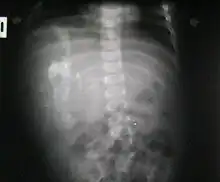

Fetus in fetu (or foetus in foetu) is a rare developmental abnormality in which a mass of tissue resembling a fetus forms inside the body of its twin. An early example of the phenomenon was described in 1808 by George William Young.[1]

A fetus in fetu can be considered alive, but only in the sense that its component tissues have not yet died or been eliminated. Thus, the life of a fetus in fetu is akin to that of a tumor in that its cells remain viable by way of normal metabolic activity. However, without the gestational conditions in utero with the amnion and placenta, a fetus in fetu can develop into, at best, an especially well differentiated teratoma; or, at worst, a high-grade metastatic teratocarcinoma. In terms of physical maturation, its organs have a working blood supply from the host, but all cases of fetus in fetu present critical defects, such as no functional brain, heart, lungs, gastrointestinal tract, or urinary tract. Accordingly, while a fetus in fetu can share select morphological features with a normal fetus, it has no prospect of any life outside of the host twin. Moreover, it poses clear threats to the life of the host twin on whom its own life depends.[4]

Fetus in fetu may be a parasitic twin fetus growing within its host twin. Very early in a monozygotic twin pregnancy, in which both fetuses share a common placenta, one fetus wraps around and envelops the other. The enveloped twin becomes a parasite, in that its survival depends on the survival of the host twin, by drawing on the host twin's blood supply. The parasitic twin is anencephalic (without a brain) and lacks some internal organs, and as such is unable to survive on its own. As the host twin has to "feed" the enveloped twin from the nutrients received over a single umbilical cord, they usually die before birth.